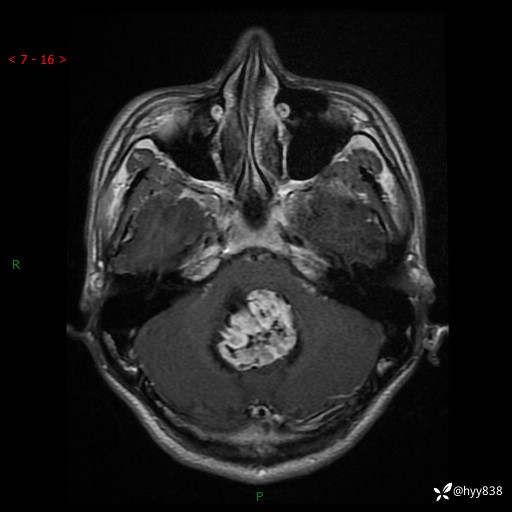

性别:男

年龄:17岁

简要病史:头痛伴间断性呕吐1月余,外院CT提示颅脑占位

颅脑MRI平扫+增强